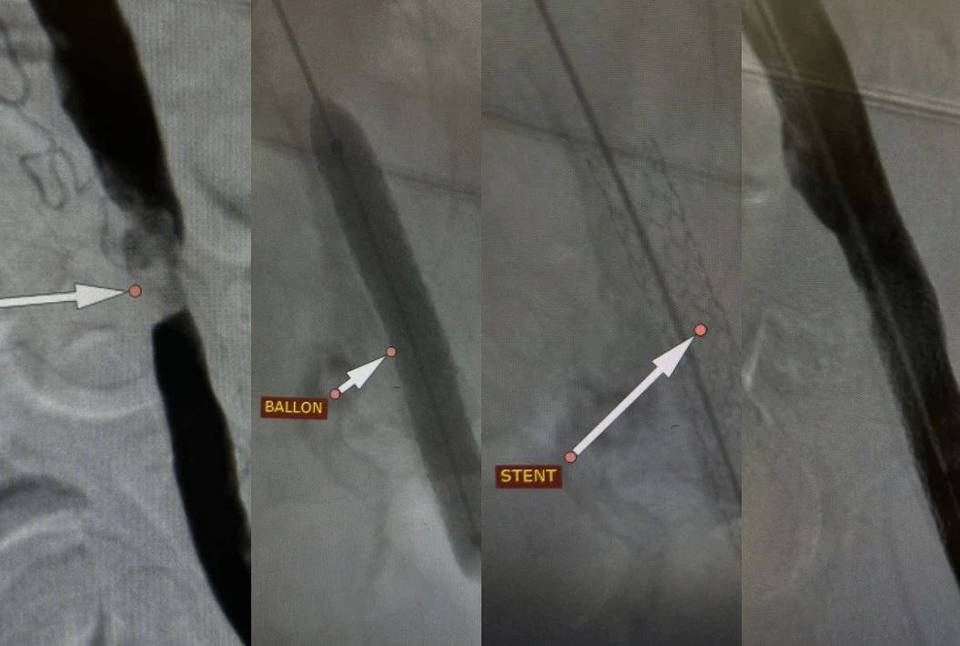

Мы выполнили стентирование подвздошной артерии, которое позволило быстро нормализовать кровообращение в нижней конечности. Уже спустя сутки пациент смог самостоятельно передвигаться и покинул стационар с рекомендациями для дальнейшего восстановления здоровья, - рассказал заведующий отделением рентгенохирургических методов диагностики и лечения Андрей Легкий.

Процедура проводилась под местной анестезией через небольшой прокол в бедренной артерии. В ходе операции был введен и расширен баллонный катетер, а затем установлен стент для поддержания просвета сосуда.